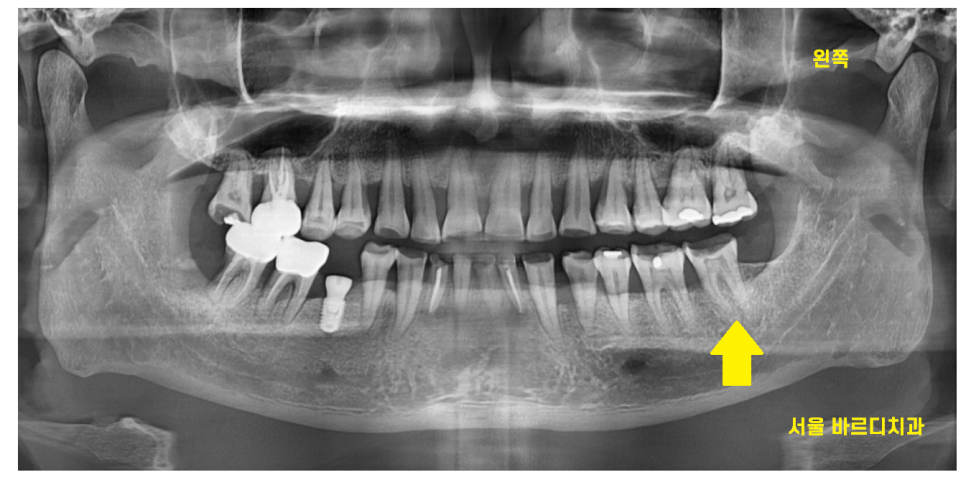

22.04.26

신경이 살아있기에

치아가 통증을 느끼는 거라서

많이 파인 치아를 망월동 치과에서

신경치료 하였습니다.